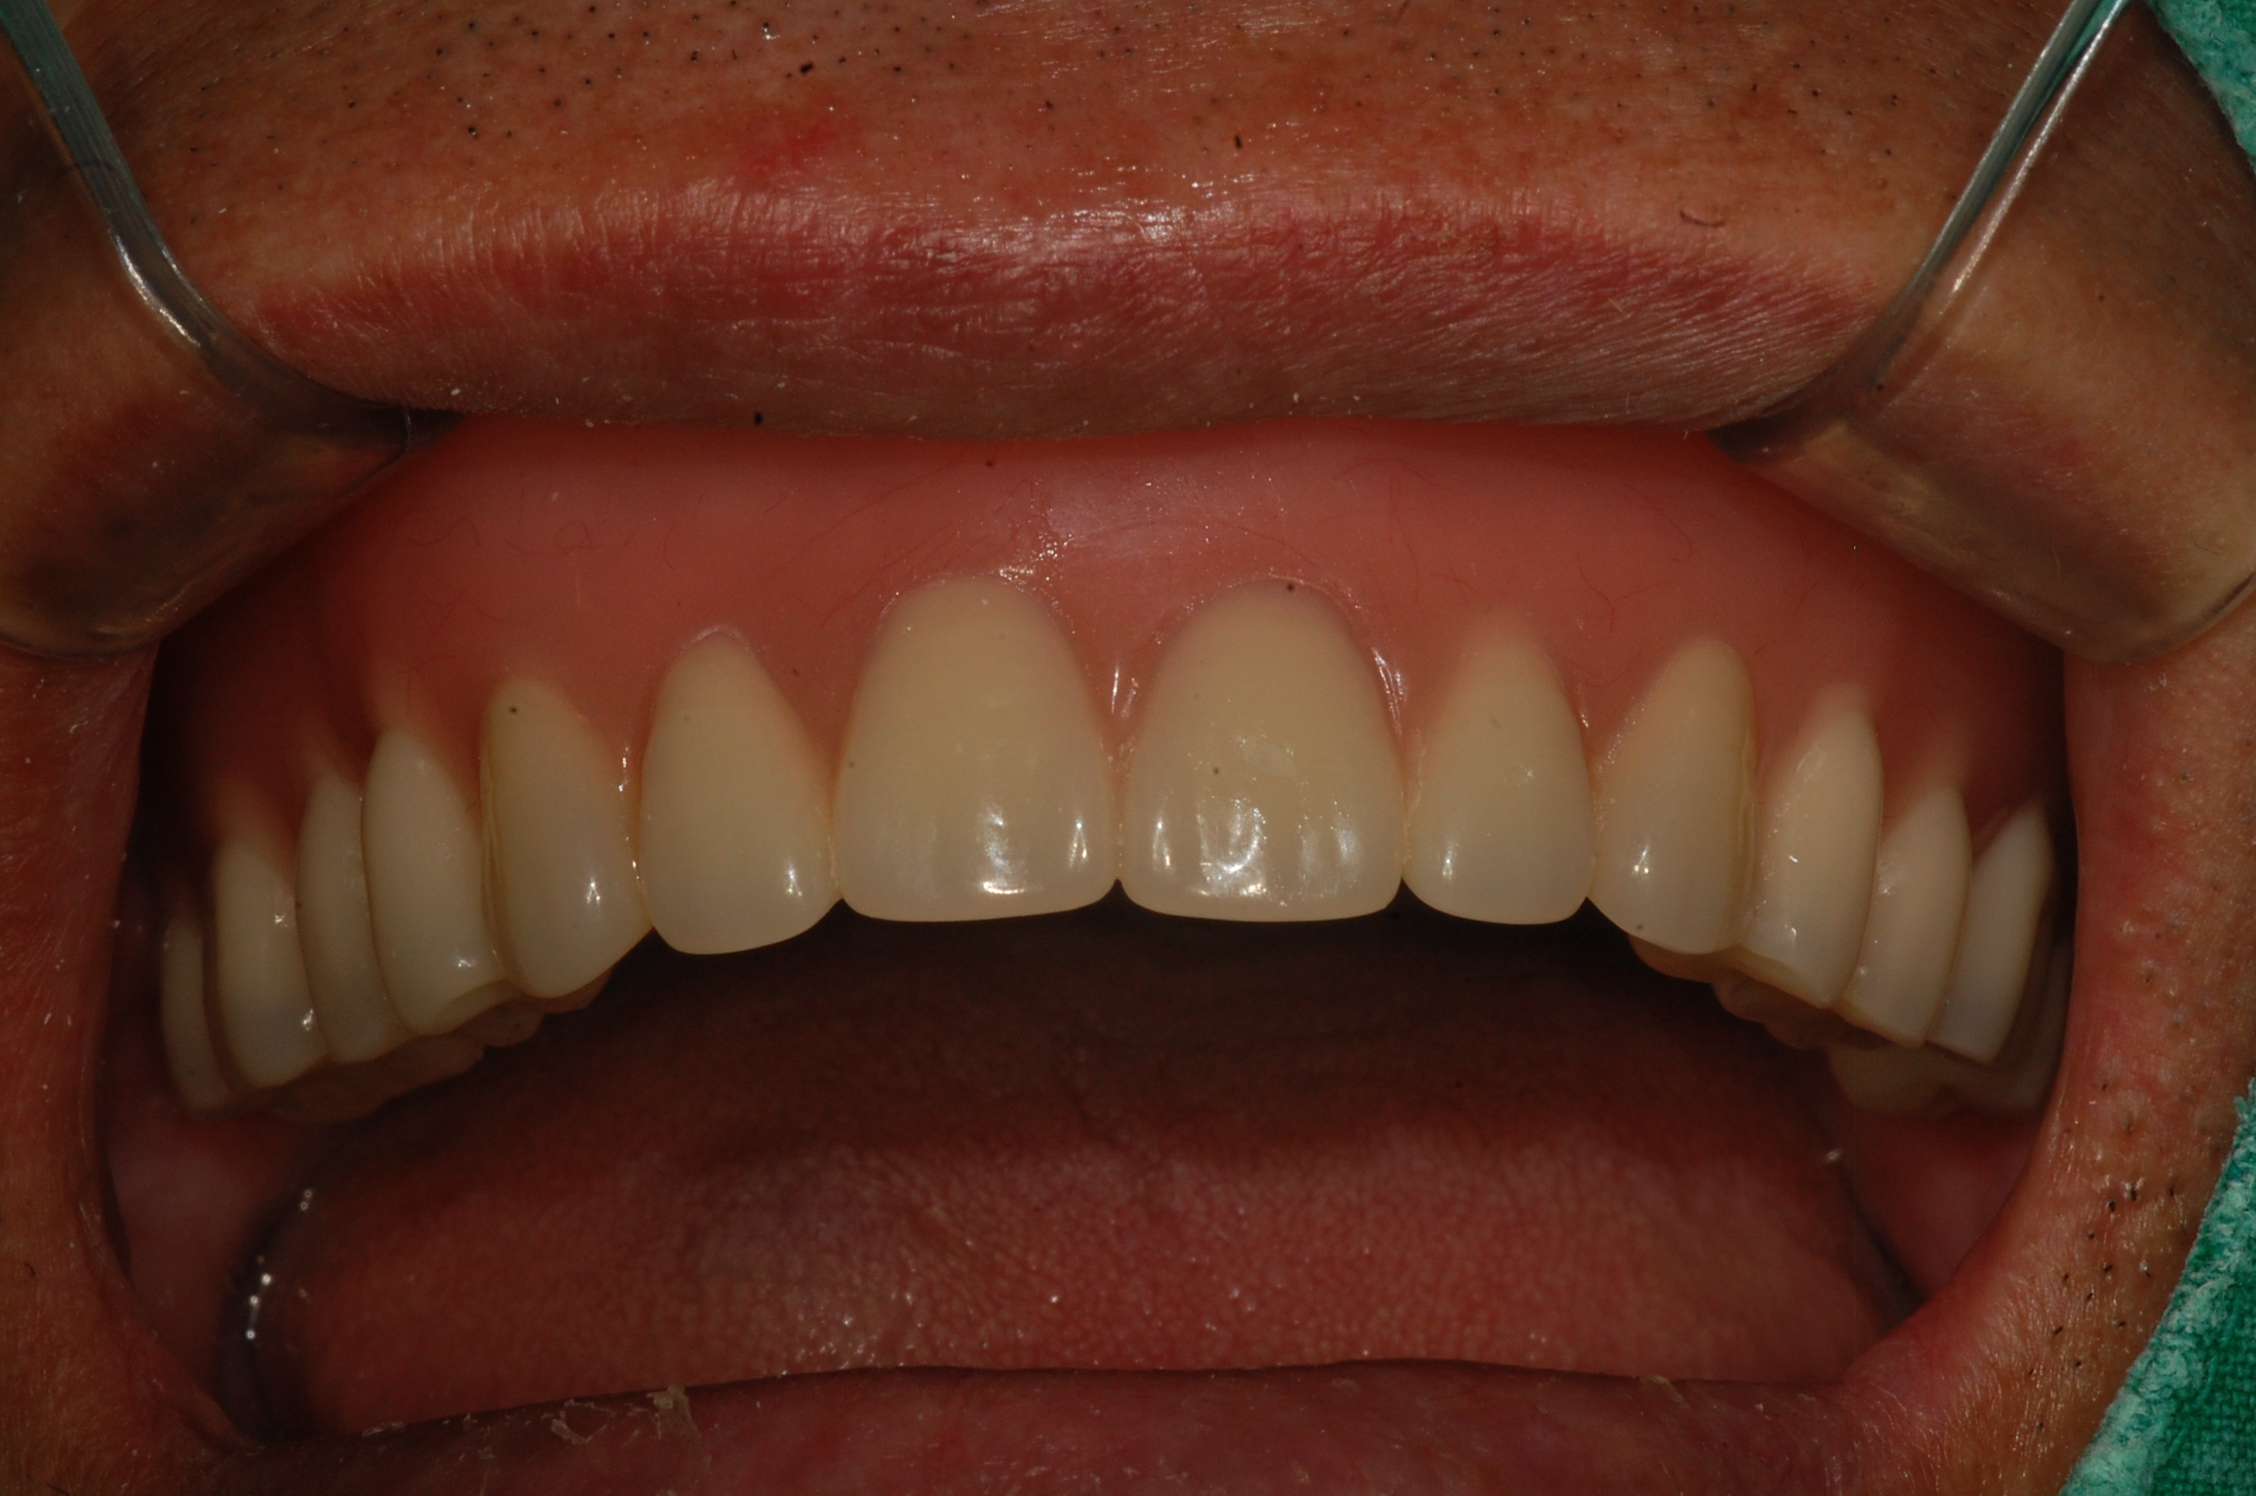

임플란트 지지틀니입니다.

임플란트에 똑딱이 같은 장치를 달아서 틀니를 쓰기 편하게 하는 방법입니다.